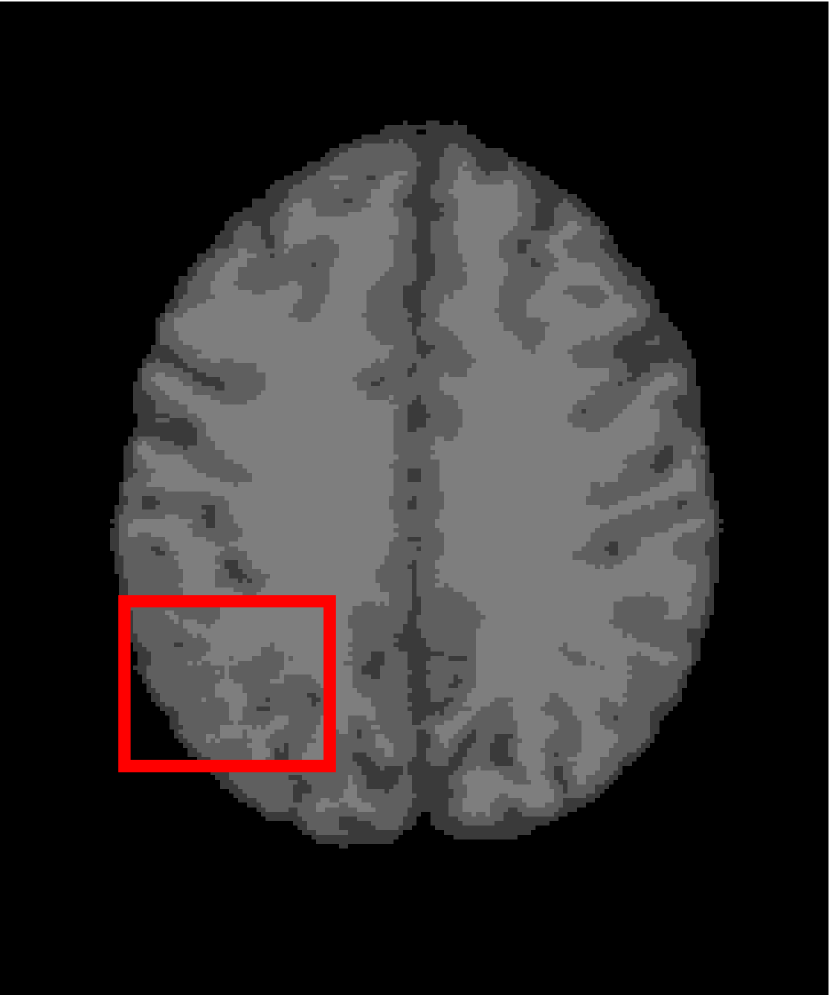

In the second experiments, we segment two medical images coming from a simulated brain database (BrianWeb): http://www.bic.mni.mcgill.ca/brainweb/. The two images are generated by T1 modality with slice thickness of 1mm resolution, 9% noise and 20% intensity non-uniformity. Here, the two images are represented two slices in the axial plane with the sequence of 100 and 110. Moreover, there are golden standard segmentations in the dataset. We set the numbers of clusters to 4. The visual comparisons are illustrated in Figs. 6 and 7.

Figure 6: Segmentation results for the first medical image. From (a) to (l): ground truth, noisy image and results of FCM_S1, FCM_S2, FGFCM, FLICM, KWFLICM, ARKFCM, FRFCM, WFCM, DSFCM_N, and LRFCM.

By focusing on the marked red square in Figs. 6 and 7, we easily find that FCM_S1, FCM_S2, FGFCM and ARKFCM are sensitive to noise. FLICM and KWFLICM are vulnerable to severe intensity inhomogeneity. FRFCM brings overly smooth results due to the use of gray level histograms. WFCM and DSFCM_N cause several contours to change. However, LRFCM acquires clear contours and suppresses noise adequately. Moreover, we find that the segmentation result of LRFCM is closer to ground truth.